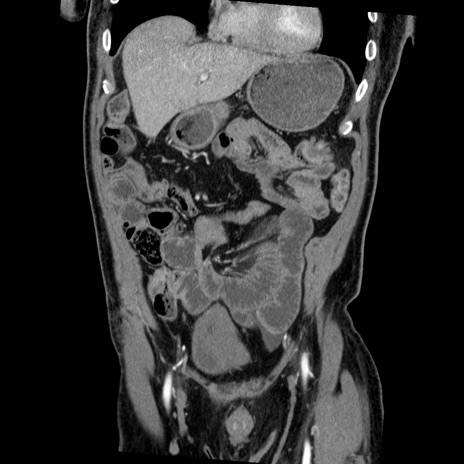

症例22(冠状断像)

【症例】50歳代男性

【主訴】腹痛

【現病歴】AVMからの被殻出血のため回復期リハ病棟入院中。 本日午後3時頃急に下腹部痛が出現した。

【既往歴】AVM、被殻出血、虫垂炎、高血圧

【身体所見】意識晴明、左半身不全麻痺、会話の理解は良好、36.5°C、腹部:膨隆、全体に板状硬、下腹部正中に圧痛点あり、反跳痛-、筋性防御不明、右下腹部にope scar

【データ】WBC 9400、CRP 0.06